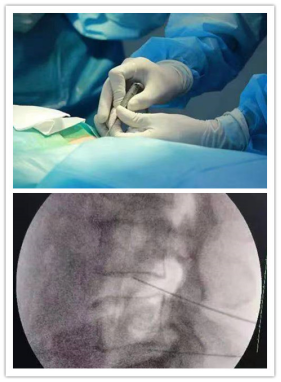

1.保守治疗无效可进行射频消融、激光、椎管内封闭等介入治疗;

2.以上疗效不佳,可进行椎间孔镜微创治疗;